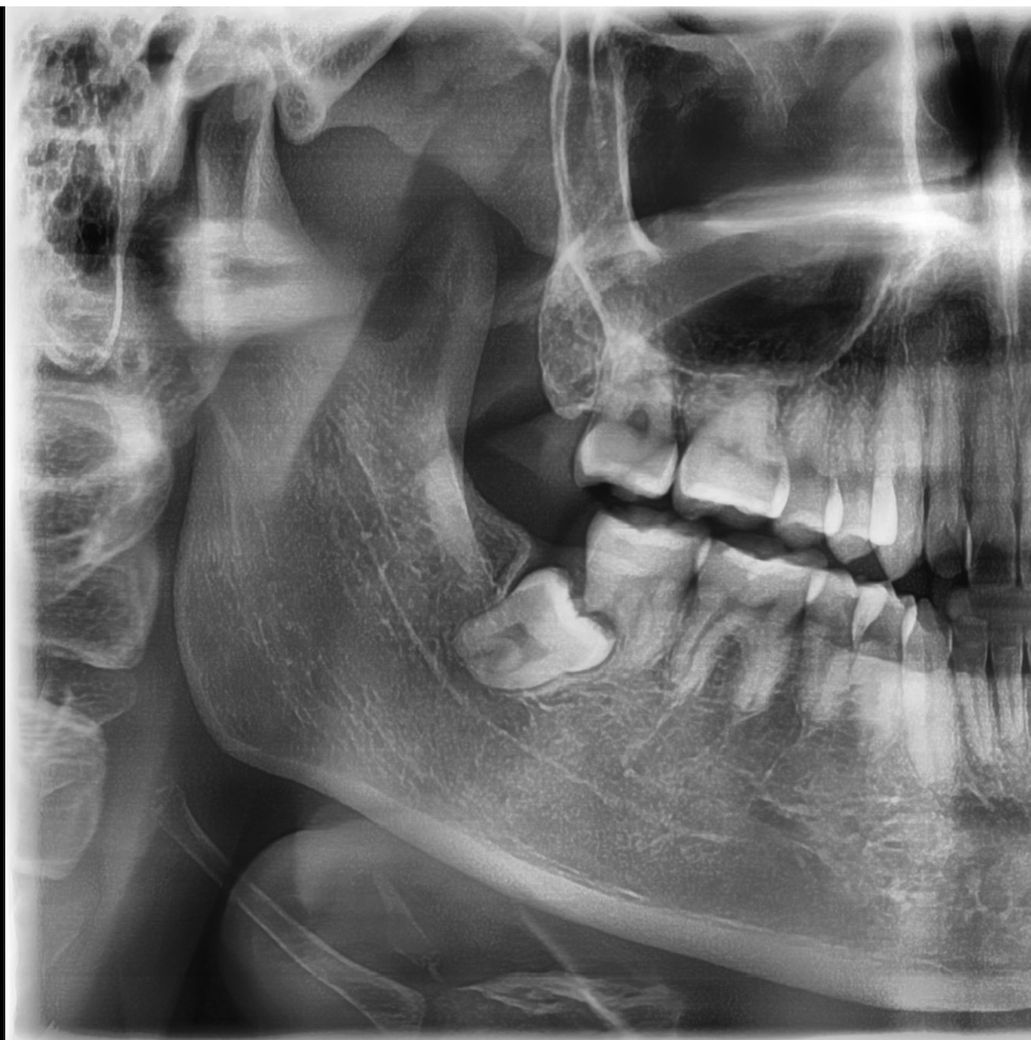

아래 사진같은 상황이고, CT 찍어보니 옆에 어금니 뿌리 하나의 반정도가 흡수된 상황이라고 하는데, 통증이 전혀없어서 어떻게 해야할지 고민되는 상황입니다. 통증이 없으면 그냥 놔둬도 된다하시는 분도 있던데, 발치없이 그냥 놔둬도 괜찮을까요? 현재 나이는 20대 초반입니다.

• 1번 째 사진

사진에 보이는 사랑니는 별다른 이유가 없다면 발치를 안하셔도 될것같습니다. 발치를 하게되면 앞치아도 같이 발치를 해야될 가능성이 높아 보입니다.

사진처럼 완전히 매복되어 있으며 특별한 문제를 발생시키지 않는 사랑니라면 굳이 발치를 할 필요는 없습니다

통증이 없다해도 이미 사랑니로 인해 그 앞 어금니의 뿌리가 많이 녹았습니다. 이미 지금 상태에서도 어금니도 오래 못쓰고, 뼈도 곧 많이 녹을 것 같네요. 지금 추천할 수 있는 건 사랑니를 이용한 자가치아이식술인데 그것도 쉽지는 않습니다. 대학병원 가보세요